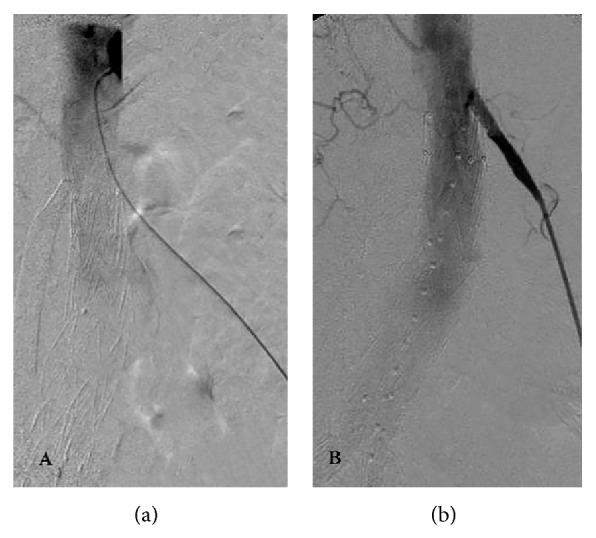

The purpose of this paper is to report a salvage maneuver for accidental coverage of both renal arteries during endovascular aneurysm repair (EVAR) of an infrarenal abdominal aortic aneurysm (AAA). A 72-year-old female with a 6 cm infrarenal abdominal aortic aneurysm was treated by endovascular means with a standard bifurcated graft. Upon completing an angiogram, both renal arteries were found to be accidentally occluded. Through a left percutaneous brachial approach, the right renal artery was catheterized and a chimney stent was deployed; however this was not possible for the left renal artery. A retroperitoneal surgical approach was therefore carried out with a retrograde chimney stent implanted to restore blood flow. After three months, both renal arteries were patent and renal function was not different from the baseline. Both endovascular with percutaneous access via the brachial artery and open retroperitoneal approaches with retrograde catheterization are feasible rescue techniques to recanalize the accidentally occluded renal arteries during EVAR.

本文旨在报告在肾下腹主动脉瘤(AAA)的血管内动脉瘤修复术(EVAR)期间,对双侧肾动脉意外覆盖的一种挽救策略。一名72岁患有6厘米肾下腹主动脉瘤的女性接受了标准分叉移植物的血管内治疗。完成血管造影后,发现双侧肾动脉均被意外闭塞。通过左经皮肱动脉入路,对右肾动脉进行了插管并植入了烟囱支架;然而,左肾动脉无法进行此操作。因此,采用了腹膜后手术入路,植入逆行烟囱支架以恢复血流。三个月后,双侧肾动脉通畅,肾功能与基线无差异。经肱动脉经皮入路的血管内方法以及逆行插管的开放腹膜后入路,都是在EVAR期间使意外闭塞的肾动脉再通的可行挽救技术。